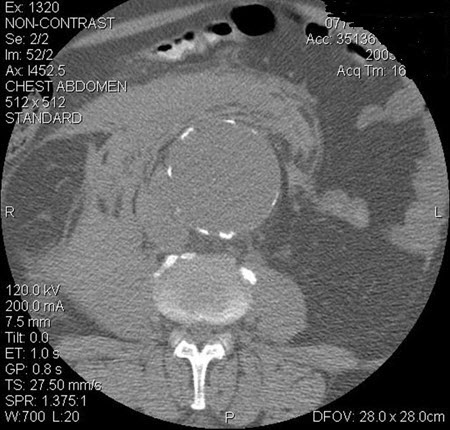

Abscesso hepático: tomografia computadorizada (TC) do abdome sem contraste mostrando um enorme abscesso hepático com gás (seta)

Adaptado de BMJ Case Reports 2009 (doi:10.1136/bcr.08.2008.0638)